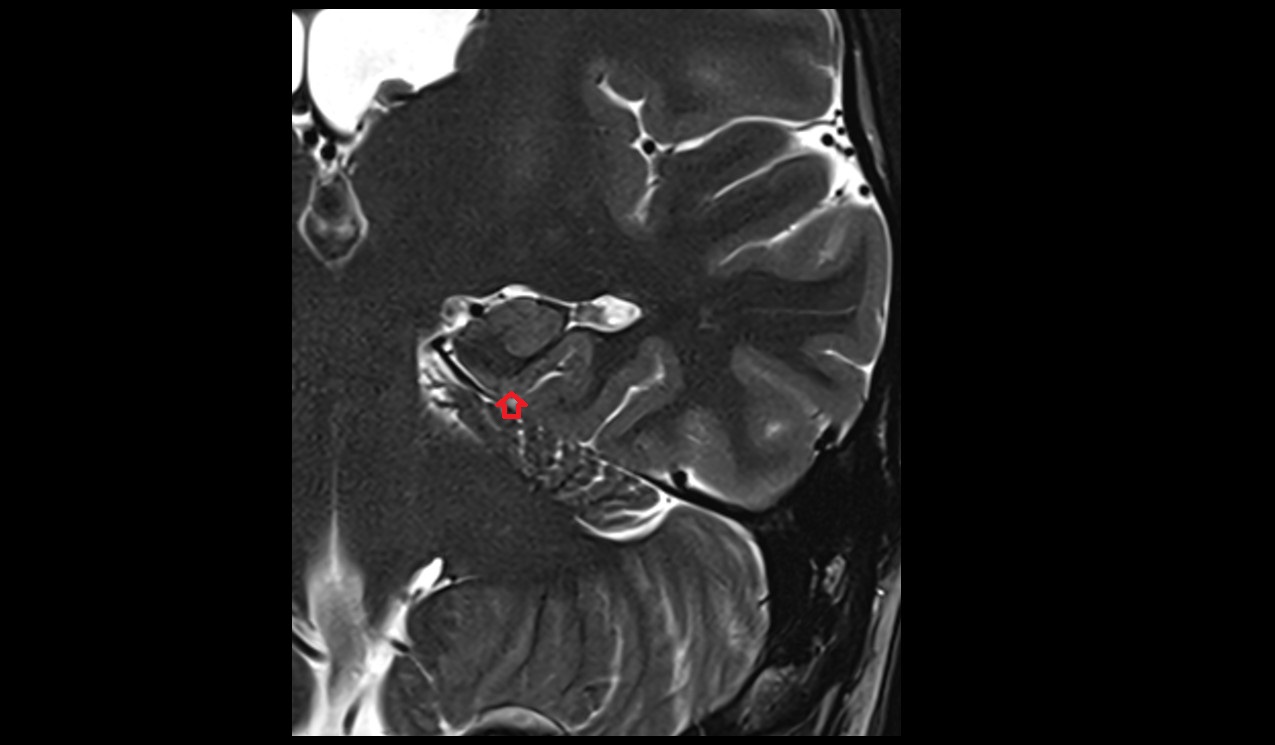

- Body of hippocampus

- Head of hippocampus

- Tail of hippocampus

- Hippocampus